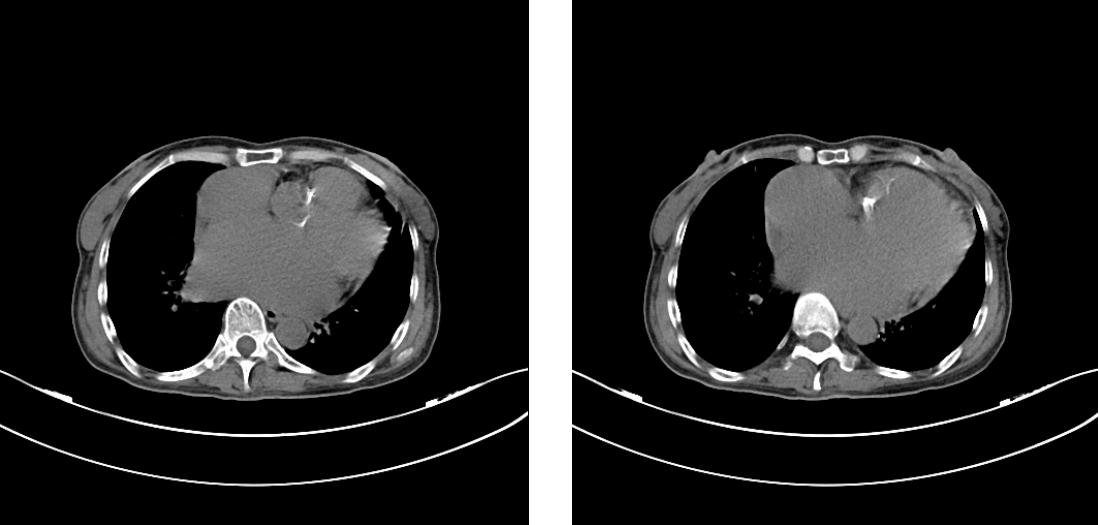

主动脉瓣及瓣环明显钙化

术前二尖瓣、主动脉瓣情况

术后主动脉瓣、二尖瓣情况